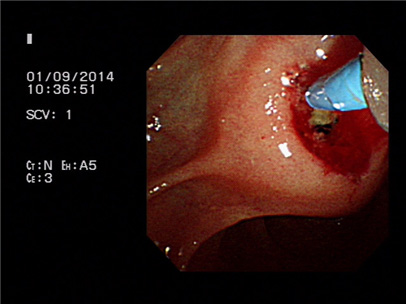

증례 2. 황달로 내원하여 유두부 결석 진단하에 담도내시경을 이용한 결석 제거술 시행 1예.